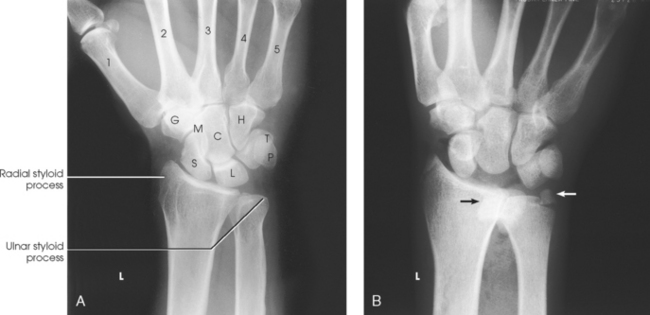

The wrist has eight carpal bones, which are fitted closely together and arranged in two horizontal rows (see Fig. 4-1). The carpals are classified as short bones and are composed largely of cancellous tissue with an outer layer of compact bony tissue. These bones, with one exception, have two or three names; this atlas uses the preferred terms (see box). The proximal row of carpals, which is nearest the forearm, contains the scaphoid, lunate, triquetrum, and pisiform. The distal row includes the trapezium, trapezoid, capitate, and hamate.

Each carpal contains identifying characteristics. Beginning at the proximal row of carpals on the lateral side, the scaphoid, the largest bone in the proximal carpal row, has a tubercle on the anterior and lateral aspect for muscle attachment and is palpable near the base of the thumb. The lunate articulates with the radius proximally and is easy to recognize because of its crescent shape. The triquetrum is roughly pyramidal and articulates anteriorly with the hamate. The pisiform is a pea-shaped bone situated anterior to the triquetrum and is easily palpated.

Beginning at the distal row of carpals on the lateral side, the trapezium has a tubercle and groove on the anterior surface. The tubercles of the trapezium and scaphoid constitute the lateral margin of the carpal groove. The trapezoid has a smaller surface anteriorly than posteriorly. The capitate articulates with the base of the third metacarpal and is the largest and most centrally located carpal. The wedge-shaped hamate exhibits the prominent hook of hamate, which is located on the anterior surface. The hamate and the pisiform form the medial margin of the carpal groove.

Structures shown: A PA projection of the carpals, distal radius and ulna, and proximal metacarpals is shown (Fig. 4-70). The projection gives a slightly oblique rotation to the ulna. When the ulna is under examination, an AP projection should be taken.